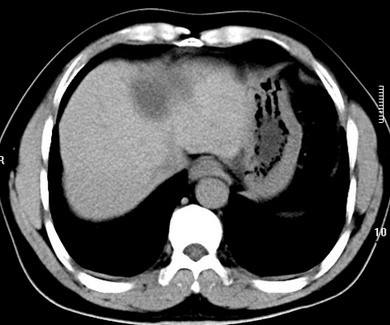

标题: CT19720:肝右叶血管瘤。肝左叶内侧段病灶考虑什么? [打印本页]

标题: CT19720:肝右叶血管瘤。肝左叶内侧段病灶考虑什么?

男,48岁,肝区不适月余,伴隐痛。

支持右叶血管瘤,左叶病灶考虑肝腺瘤。

1)不排除肝左叶肝癌。2)肝右叶血管瘤。

肝左叶炎性病变,肝癌待排。2)肝右叶血管瘤。

1.肝右叶血管瘤;2.肝左叶炎性假瘤?肝癌?建议穿刺活检.

右叶病灶典型,左叶病变慢性炎块

1、肝右叶血管瘤(典型)。

2、肝左叶病灶,强化不明显,疑炎性假瘤,建议结合临床并密切随访。

1、肝左叶炎性病变,肝癌待排。

2、肝右叶血管瘤。

肝左叶脓肿,肝癌待排。2)肝右叶血管瘤